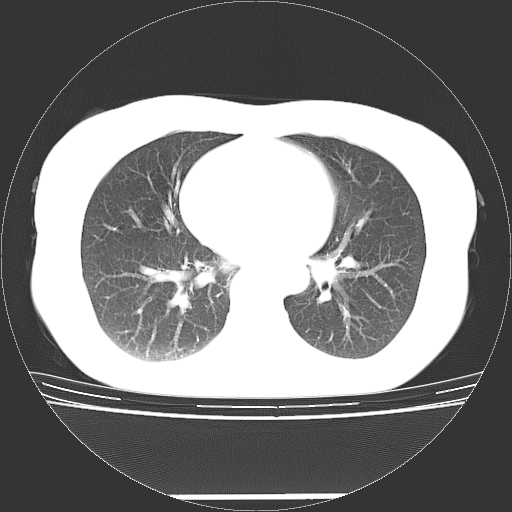

标题: CT27224:女,43岁,体检发现左肺下叶结节影。 [打印本页]

女,43岁,体检发现左肺下叶结节影。

左下肺外带胸膜下见孤立实性均匀密度结节影,边缘光整,增强呈渐进性强化,病灶吴分叶征及毛刺征象;支持硬化性血管瘤。

左肺下叶基底段圆形结节,多考虑:错构瘤>硬化性血瘤>炎症假瘤>周围性肺癌!期待结果!

左肺下叶外侧基底段圆形结节,多考虑:错构瘤>硬化性血瘤>炎症假瘤>周围性肺癌!期待结果!

良性结节,有钙化,强化不明显,考虑软骨性错构瘤。

左肺下叶外基底段良性结节(错构瘤?)。